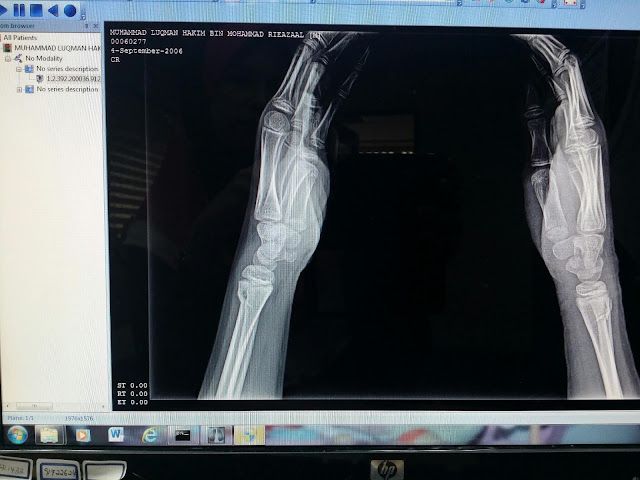

kecederaan : patah kedua2 pergelangan tangan

Implikasi - terpaksa simen tangan dan tak dapat ke sekolah selama sebulan.